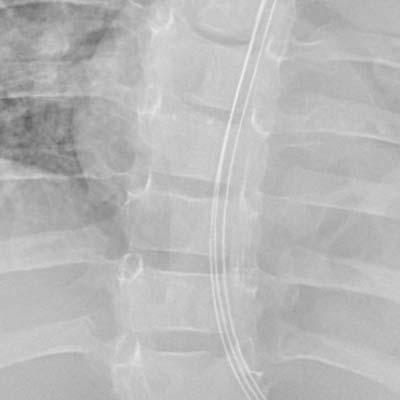

2. Comparaison de la réduction du bruit basée sur le sujet

Image de la région thoracique (enfant)

Aucun traitement

Traitement conventionnel

NR intelligent